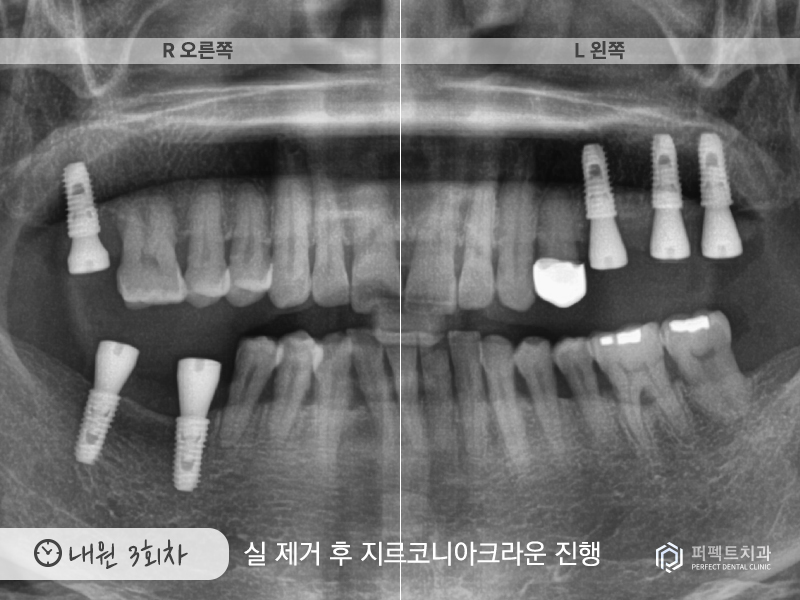

내원 3회

그리고 3번째 내원하신 날에는 실을 제거하고 지르코니아 크라운까지 진행을 하였습니다.